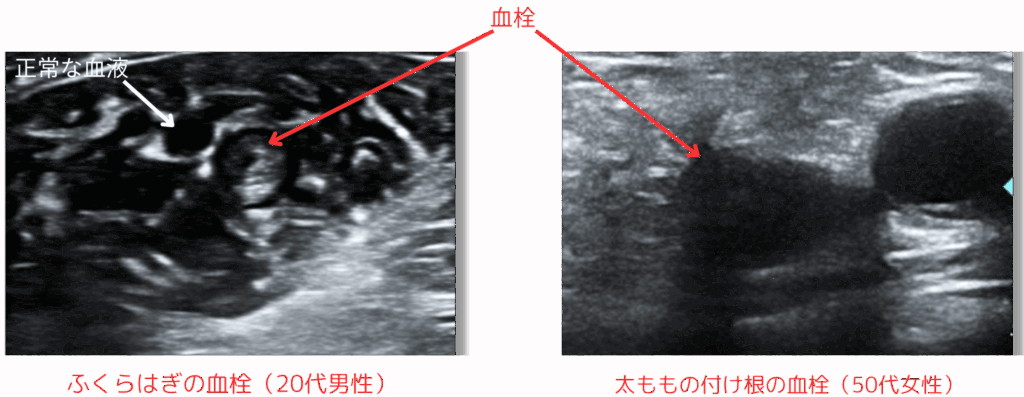

下肢の血栓(静脈)ドック

- 料金:8,800円 (税込)

- 所要時間:20〜30分程度

下肢に血栓があると、お仕事など1日中立っていた場合に夕方にはむくみという症状が出たり、剥がれた血栓が、足→心臓→肺と送られ“肺動脈”で詰まる肺塞栓といった死に至る疾患の原因になることがあります。下肢静脈をエコーで評価することで、早期発見につなげることが可能です。なお、経口避妊薬(ピル)は血栓の危険因子であることは有名です。

| 検査の種類 | 検査内容 | ||

| 理学的検査 | 問診(既往歴・業務歴)、医師診察 | ||

| 血液検査 | D-ダイマー、プロトロンビン時間(PT) | ||

| 画像検査 | 下肢深部静脈エコー |